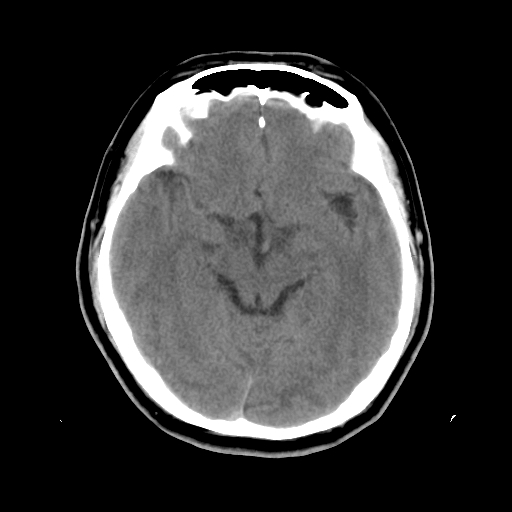

标题: CT15194:男,53岁,头痛、恶心三天。 [打印本页]

男,53岁,头痛、恶心三天。

筛窦粘液囊肿。

筛窦粘液囊肿

考虑筛窦内粘液囊肿可能性大。

支持左侧筛窦后组粘液囊肿。